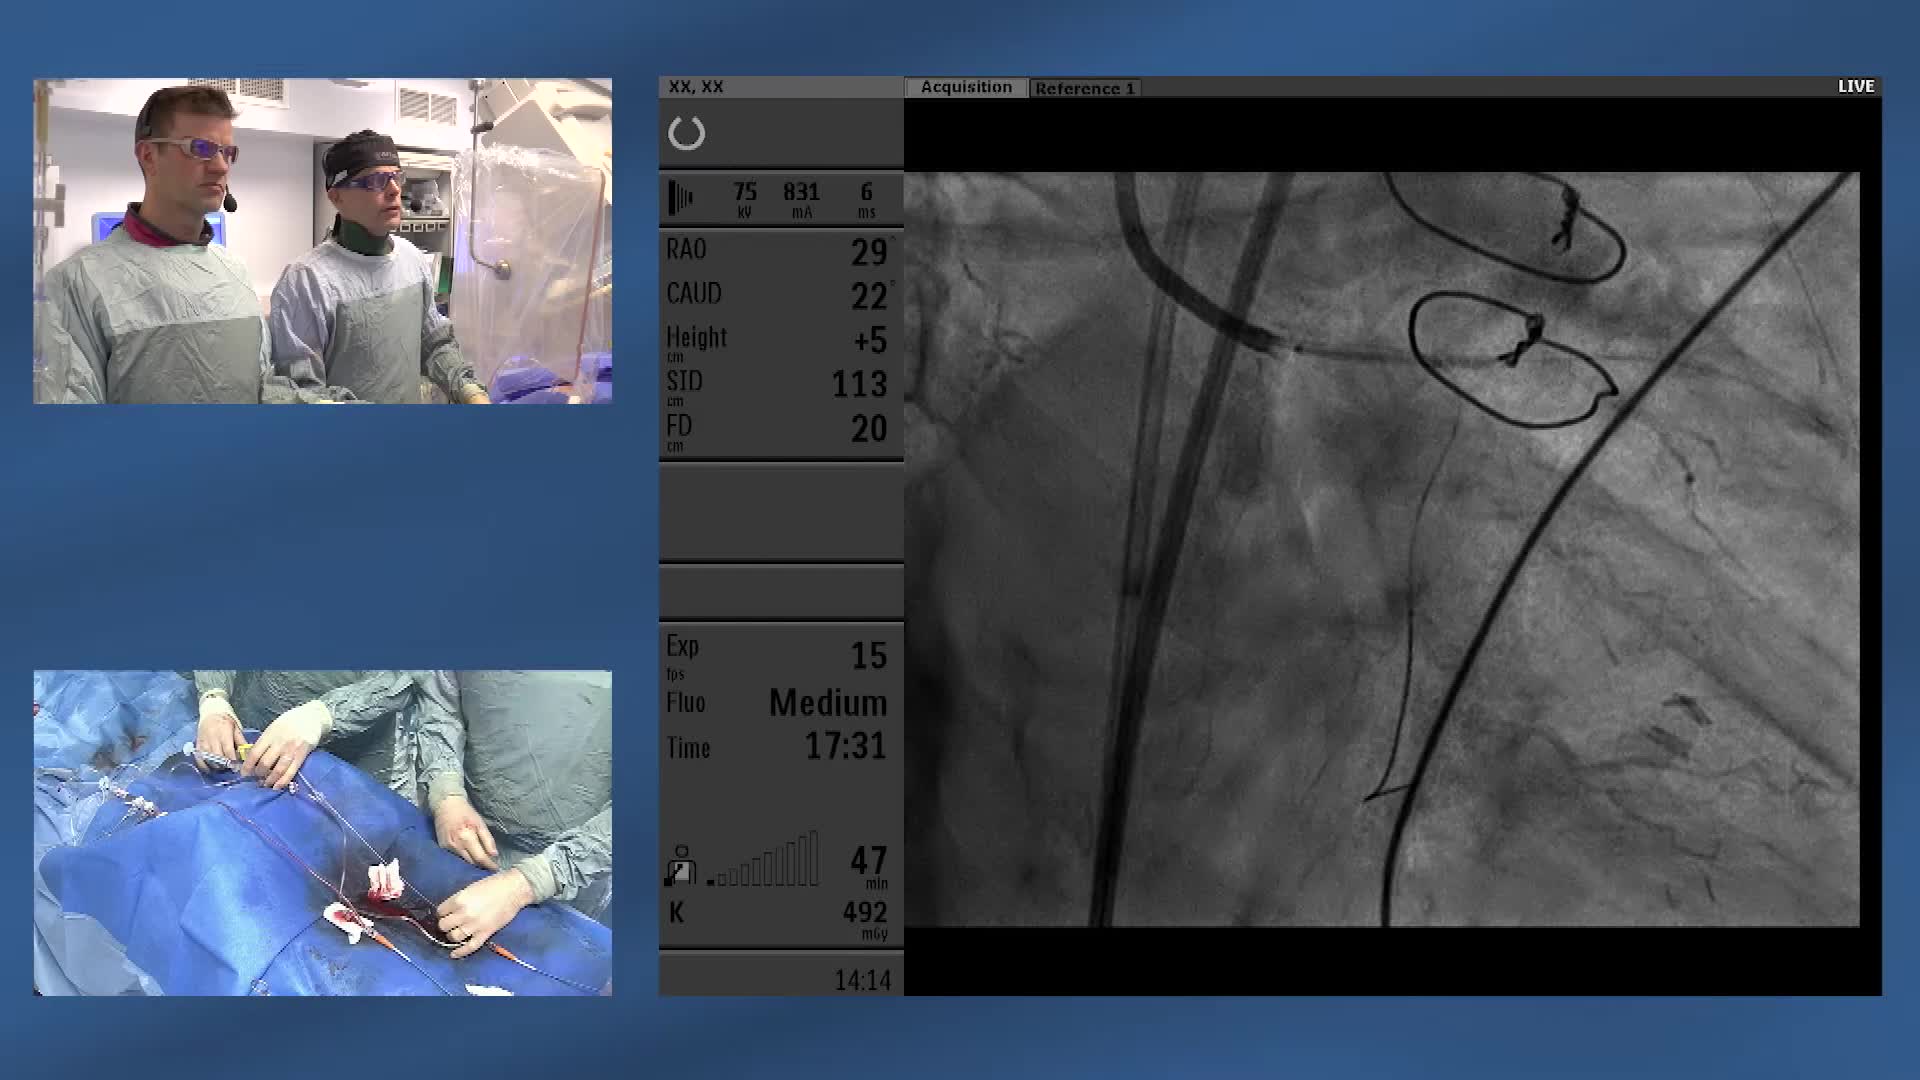

ABC for using Coronary Physiology in Aortic Stenosis, Primary Percutaneous Coronary Intervention (PPCI)/ACS, Muscle Bridges and Atrial Fibrillation w/ Dr Ricardo Petraco